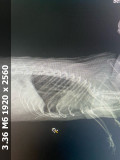

Вот снимок рентгена, сейчас дышит более менее хорошо, но видно что бока ходят. Ест хорошо, но заметил что спит внизу клетки а не сверху в гамаке как обычно было до смерти его друга Омлетушки (ОГМ)